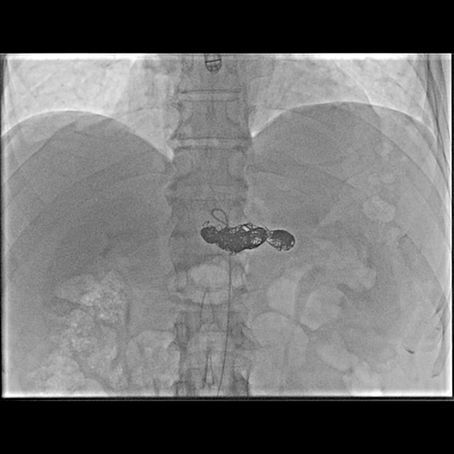

Aneurisma delle arterie viscerali

Gli aneurismi delle arterie viscerali sono una condizione rara ma clinicamente rilevante. Pur avendo un’incidenza bassa, possono evolvere in modo imprevedibile e provocare complicanze serie come la rottura o l’emorragia interna. Un aspetto che li rende particolarmente insidiosi è la loro natura silente: spesso non generano sintomi fino alle fasi avanzate e vengono scoperti in modo del tutto casuale. Negli ultimi anni l’evoluzione delle tecniche mini-invasive e dei materiali e